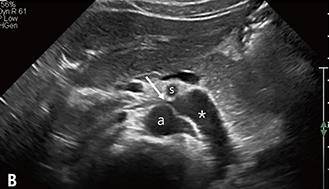

연합뉴스 보도에 따르면 호두까기증후군은 왼쪽 콩팥 정맥이 대동맥과 상장간동맥 사이에서 눌려 콩팥 안에 압력이 증가하면서 미세한 콩팥 조직과 혈관에 손상이 생기는 질환을 일컫는다.

호두까기증후군이라는 질환명은 두 동맥이 콩팥 정맥을 누르는 모양새가 마치 호두까기 기계의 집게처럼 보이고, 콩팥 정맥이 호두처럼 보인다고 해서 붙여졌다.